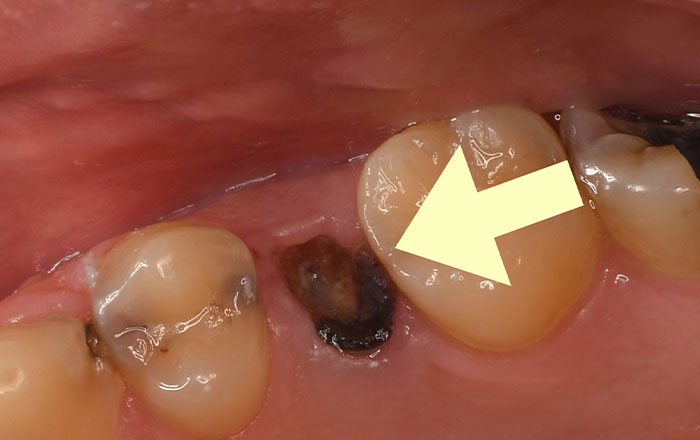

酸が歯を溶かして、やがて歯に穴が空いてしまうと「むし歯」になります。

ですが、脱灰が起きたからといって、すぐにむし歯になるというわけではありません。